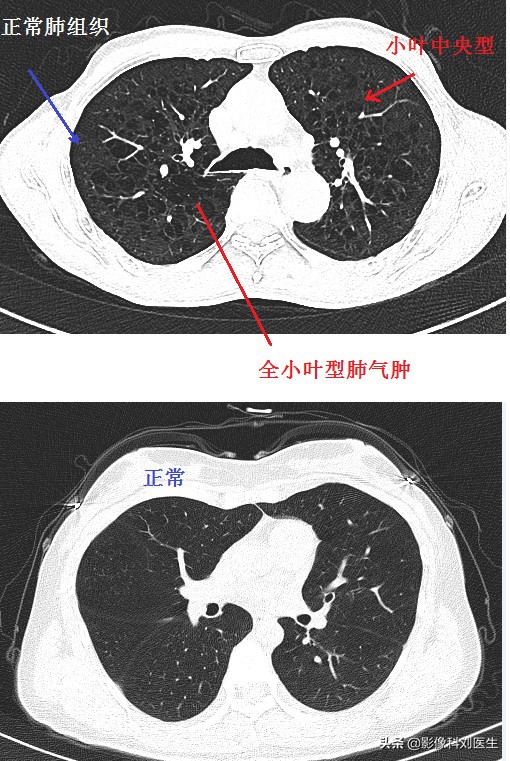

首先给大家看几张CT图像:

通过上面的图像,相信大家有了一个大概的印象。肺气肿主要征象即为正常肺组织内出现无囊壁的低密度区。

首先,我们来看小叶中央型肺气肿。它是一种与吸烟相关的肺部疾病,主要累及肺上叶、呼吸性细支气管破坏融合,肺泡导管肺泡囊正常,在CT上主要表现为散在分布的小圆形、无壁的低密度区,直径一般约2-10mm,位于肺小叶中央,仍可见小叶核心内的动脉。

其次,我们再来看一看全小叶型肺气肿。它形成的重要原因是抗胰蛋白酶缺乏,表现为终末细支气管远端气腔的全部破坏、扩大,累及整个腺泡,弥漫分布于整个肺野;在CT上,主要为广发分布的无壁低密度区,大小和形态多不规则,病变区内的血管影明显变细、变少,肺气肿样改变通常在肺基底部。